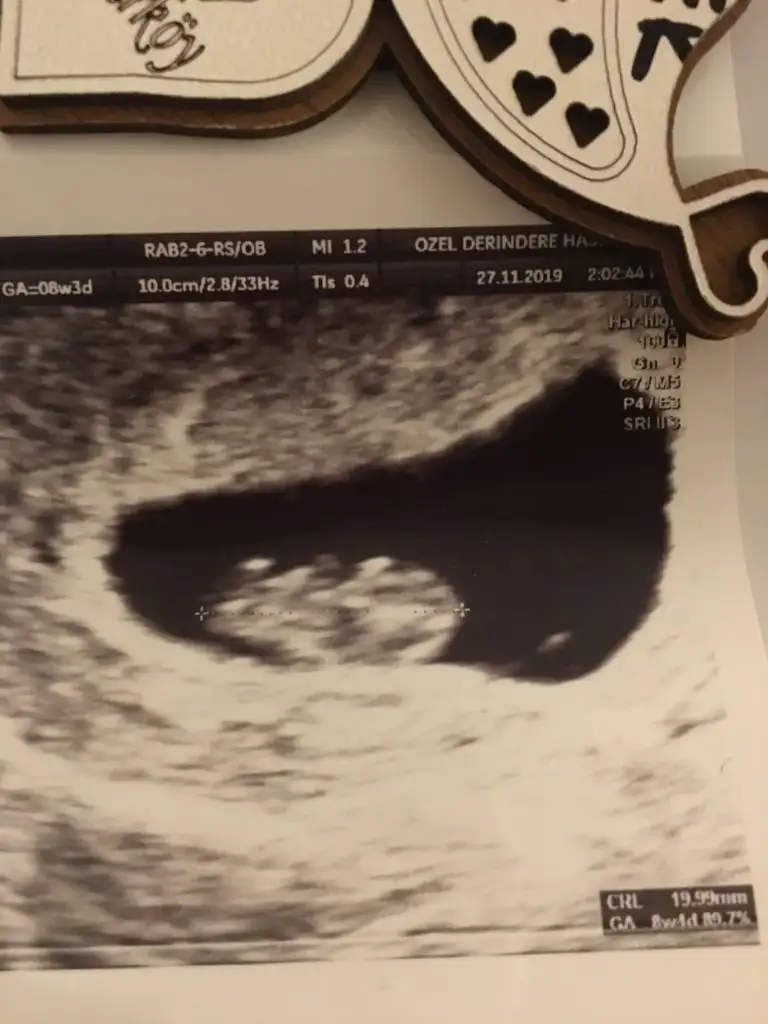

Bu da venim 12 haftalık ultrasonum.Doktor bir dahaki sefere anlaşılır dedi ama tahmin edebilirseniz çok sevinirim.